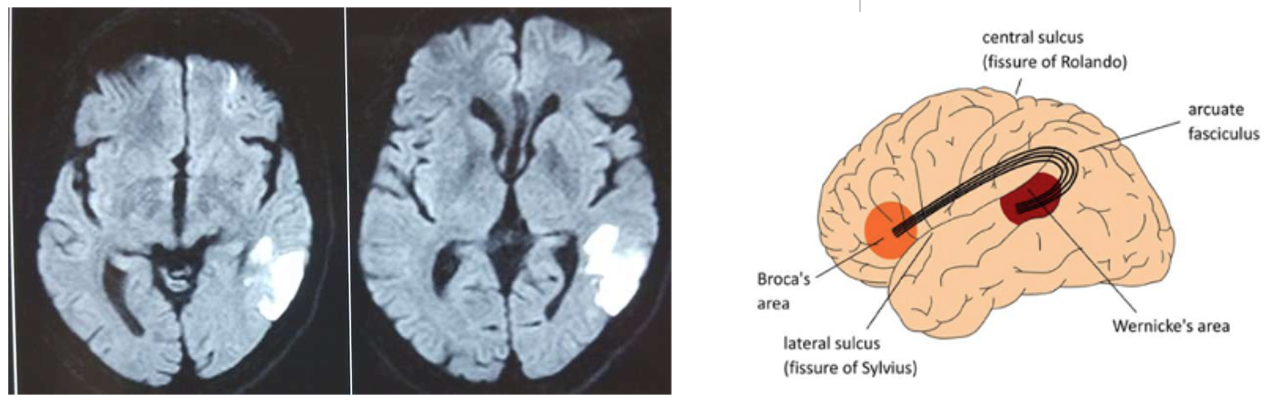

Wernickes Aphasia

Affects a person’s ability to understand and produce meaningful speech

Language comprehension is impaired

*Fluent

*Paragrammatism (disordered grammar)

Paraphasia (replace phoneme or word withanother)

Neologism (generate nonsense words)

*Jargon (substitute non-related word/phrase)

* Comprehension (impaired understanding)

Conduction Aphasia

Impaired repetition of speech

Also inability to produce appropriate responses to heard communication (even though the communication is understood

Global Aphasia

Impaired ability to produce, understand, & comprehend language

Someone with global aphasia would experience difficulty:

Speaking or repeating words/phrases

Understanding simple words/phrases

With spelling & grammar

Understanding figurative language

Can be caused by a stroke or traumatic brain injury